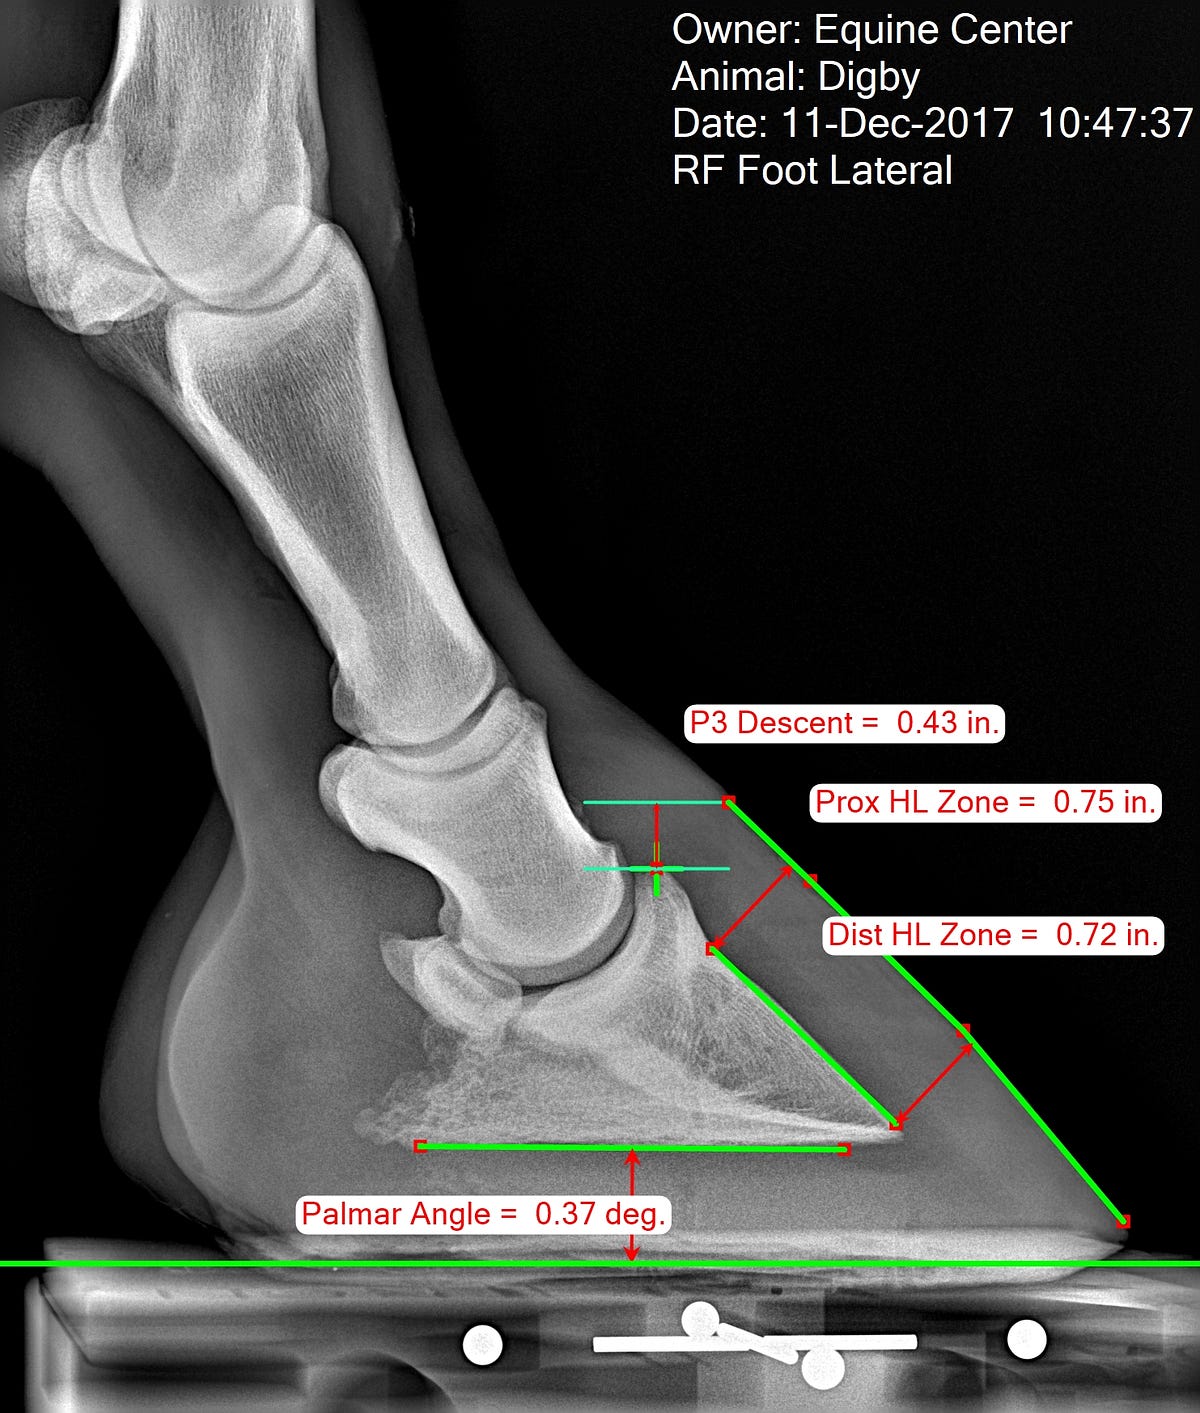

Metron Hoof Xray Mark Ups (2 feet series) Six BarTherapy

From sixbartherapy.com

Metron Hoof Xray Mark Ups (2 feet series) Six BarTherapy Horse Hoof X Ray Cost Carried out at the vet hospital so no call out. i paid nearly £1000 for a lameness check and x rays of hocks, stifles and an ultrasound of the suspensories. learn about the machines and technologies your veterinarian can use to look inside your horse, including mri, ct, pet scans, and more. a veterinarian explains why hoof. Horse Hoof X Ray Cost.

Measuring the Equine Hoof in Radiographs — a Focus on Calibration by Horse Hoof X Ray Cost Computed tomography (ct), diagnosing hoof lameness. Carried out at the vet hospital so no call out. i paid nearly £1000 for a lameness check and x rays of hocks, stifles and an ultrasound of the suspensories. learn about the machines and technologies your veterinarian can use to look inside your horse, including mri, ct, pet scans, and more.. Horse Hoof X Ray Cost.

From medium.com

Measuring the Equine Hoof in Radiographs — a Focus on Calibration by Horse Hoof X Ray Cost i paid nearly £1000 for a lameness check and x rays of hocks, stifles and an ultrasound of the suspensories. Your horse may need to be sedated, depending on their temperament, to ensure the best quality image. Carried out at the vet hospital so no call out. Computed tomography (ct), diagnosing hoof lameness. learn about the machines and. Horse Hoof X Ray Cost.